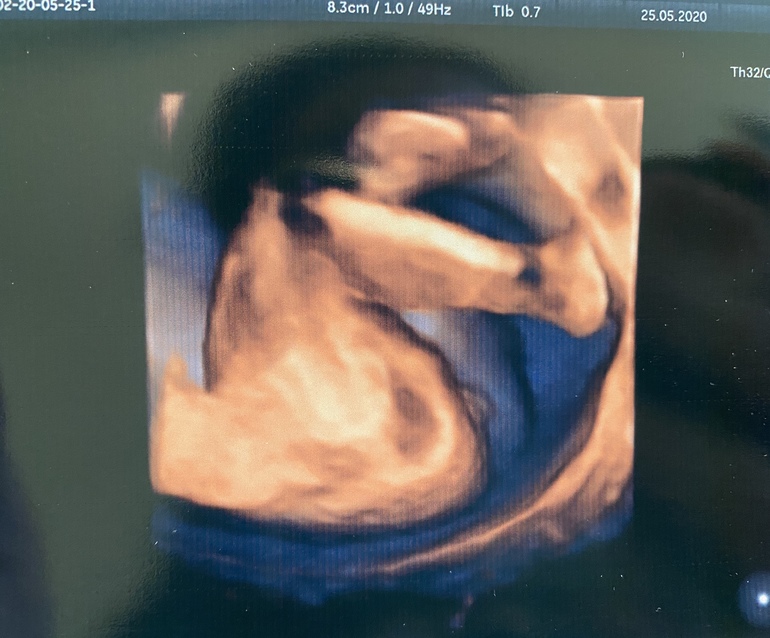

По месячным 22.2, по узи поставили ровно 22 недельки . Весим мы 526 гр, рост 28 см 🥰Девочка осталась девочкой 😌 доказательство тоже сняли 😉 все хорошо с малышкой , растём , развиваемся🙏🏻